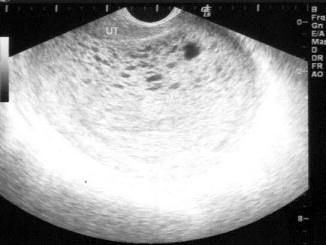

问题 女,24岁,停经2月余阴道不规则出血数日,阴式B超检查,如图所示,最可能的诊断为?(?)

选项 A.早孕 B.葡萄胎 C.绒癌 D.宫内积血块 E.畸胎瘤

答案 B